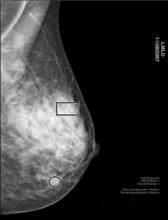

Intelerad Medical Systems introduces new tomosynthesis support for InteleViewer, enabling expanded breast imaging interpretation for the IntelePACS or InteleOne reading and reporting platforms. Using InteleViewer’s flexible hanging protocol layouts, radiologists can quickly step through cases for mammography screening or diagnosis, using tomosynthesis 3-D images to advance women’s health.

“Tomosynthesis really allows us to look through the breast, slice by slice, in a way that we haven’t been able to before,” explains Beth Whiteside, M.D., breast imaging specialist at Albany Medical Center and radiologist with Community Care Physicians. “It takes away that vexing issue of tissue overlap and allows us to look underneath. I think it is every radiologist’s dream.”